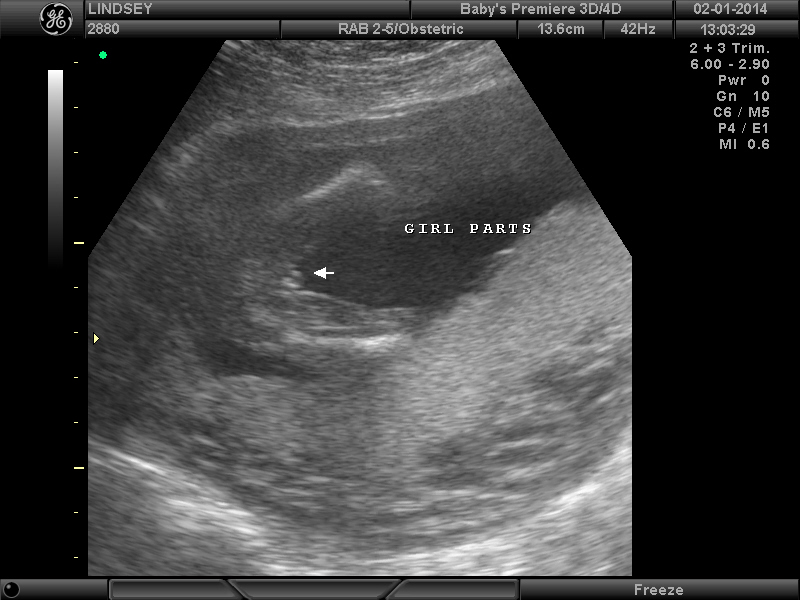

3 Attachment(s)

Help confirming 'girl' ultrasound??

So my Dr. was making me wait a while longer to find out the gender but since I was sooo impatient we went for an elective ultrasound this weekend at 18 weeks. The tech said she was sure it's a girl (yay!!) but I'm so nervous to 100% trust it because I still can't make much sense of the ultrasound myself despite her pointing parts out. (Sorry, new at this! :worry:) It just seems so hard to tell what angle she's seeing everything at. Can anyone ease my my mind and confirm that these are in fact girl parts?? I need to buy something pink!Thanks for any help!! :) :DD: Attachment 16772Attachment 16773Attachment 16774